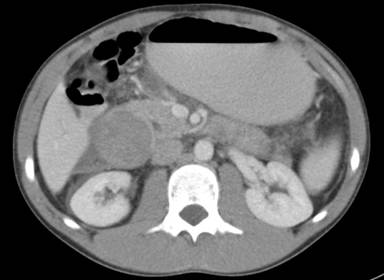

An ultrasound scan of the abdomen showed sludge in the gallbladder, but no stones. The common bile duct was dilated at 17 mm, with minimal intrahepatic duct dilatation. The pancreas was normal. There was in addition a complex retroperitoneal mass measuring 9.4x4.7x4.7 cm. A contrast enhanced CT scan of the abdomen was performed to further characterise the mass. This confirmed a large heterogeneous peri-duodenal mass in the retroperitoneum, obstructing the second part of duodenum and the bile duct (Figure 1). The pancreas was normal. The pre-operative diagnosis was one of possible gastrointestinal stromal tumour (GIST) of the duodenum with gastric and biliary obstruction. A laparotomy with a view to a pancreaticoduodenectomy was planned.

Figure 1. CT scan of the abdomen showing a rounded heterogeneous mass compressing the second part of duodenum. The bile duct is dilated and the stomach is distended. |